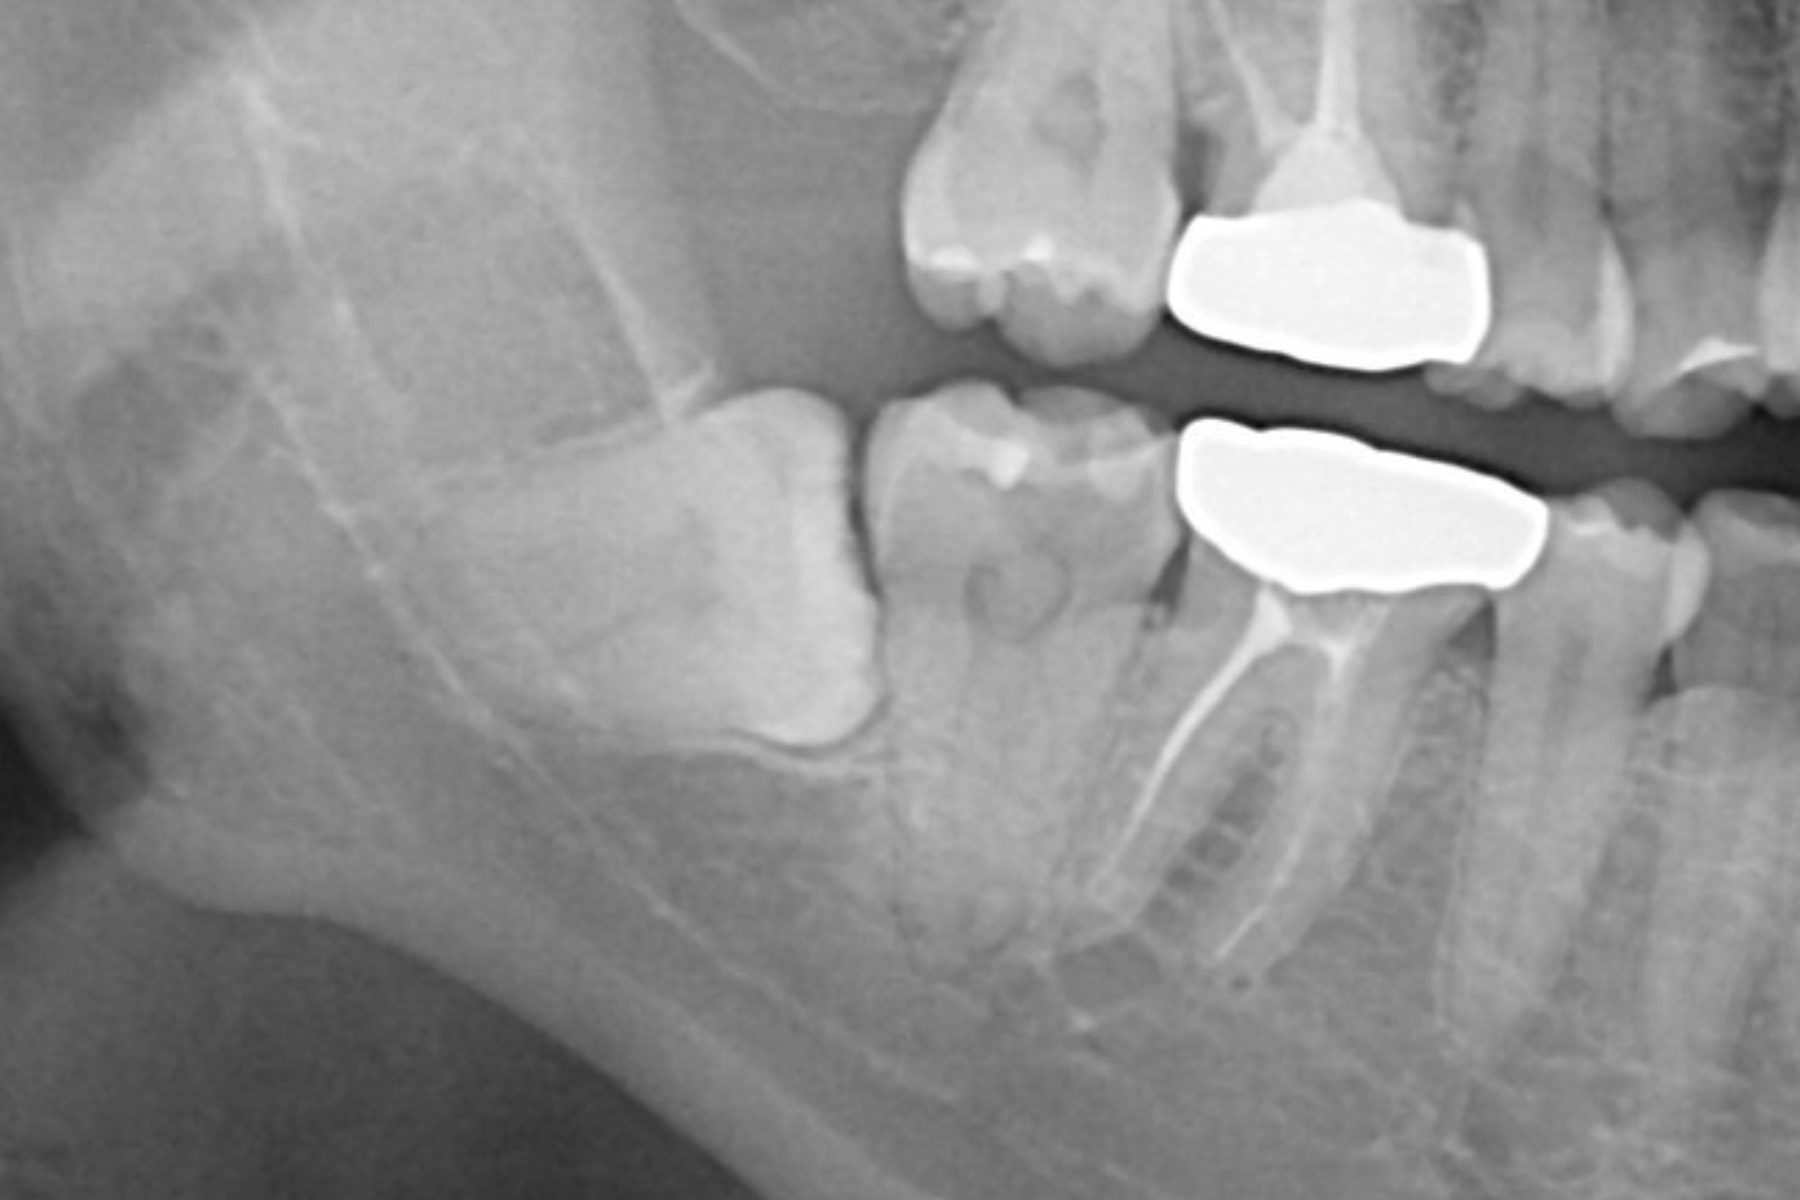

| 治療内容 | レントゲンにて親知らずは水平埋伏しており神経と近接していることがわかった。更に診査したところ神経損傷のリスクは高リスク群では無かった為説明し抜歯した。 |

| 主訴 | 右下奥歯が膿んでいる。 |

| 治療内容 | 右下7番は歯根破折により抜歯が推奨された。親知らずの状態も良かった為抜歯と同時に歯牙移植手術を実施し、実質的に機能歯の喪失を防いだ。 |